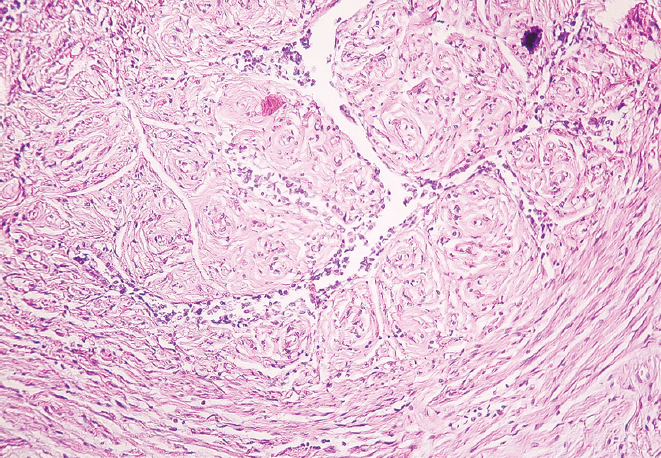

RESULTS: There was a decrease in the external diameter of the isthmus and funnel of both fallopian tubes in women from young age to old age (p < 0.01). At old age, there was a predominance of external diameter parameters of the isthmus and funnel of the right fallopian tube in comparison with those of the left fallopian tube (p < 0.01), while at young age there was only a tendency for the diameter of the isthmus and funnel of the right fallopian tube to predominate (p > 0.05). The histological study showed the presence of thickened folds of the mucous membrane and flattened epithelium in the studied areas in older women, thinning of the muscular membrane layers and overgrowth of connective tissue in comparison with the samples taken for the study in younger women.

CONCLUSIONS: Morphologic restructuring of the isthmus and funnel of the fallopian tubes from young to old age consists in thickening of the mucous membrane folds, flattening of the epithelium, overgrowth of connective tissue in the wall and reduction of their outer diameter with predominant parameters in the right fallopian tube.